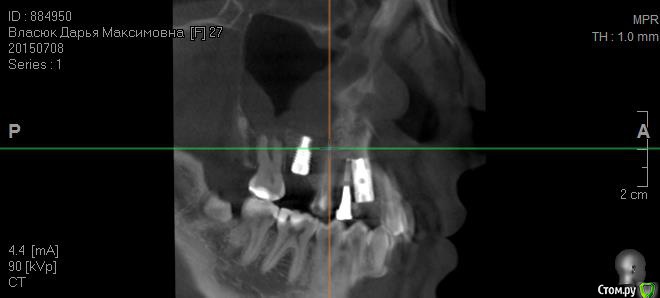

fifa888.dexo Опубликовано 22 июля, 2015 Автор Поделиться Опубликовано 22 июля, 2015 а это все что я могла придумать с кт Ссылка на комментарий

diesel87 Опубликовано 22 июля, 2015 Поделиться Опубликовано 22 июля, 2015 По ОПТГ, формирователь не докручен, вам уже сказали, имплант в области левого клыка скорее всего не в контакте с четверкой (но надо глянуть КТ), даже если четверка депульпирована, она бы четко отреагировала бы на контакт с имплантом, болью или дискомфортом при накусывании/надавливании. В области синуса воспаление не особо просматривается и материал тоже четко не визуализируется в пазухе. Капать надо сосудосуживающее или гормональное. Выложите еще раз ссылку на КТ, ваши срезы не информативны. Ссылка на комментарий

diesel87 Опубликовано 22 июля, 2015 Поделиться Опубликовано 22 июля, 2015 http://fs2.directupload.net/images/150723/9sv48h7l.jpg http://fs1.directupload.net/images/150723/9nsd29hm.jpg http://fs2.directupload.net/images/150723/q4s456ou.jpg http://fs2.directupload.net/images/150723/9x7h27mc.jpg По КТ:1.возможно имплант в области клыка в апексе (самой верхней части) контактирует с четверкой (не ясно из-за того что имплант фонит), если четверка не реагирует, то пока наблюдать, делать прицельные снимки раз в 3/6/9/12 месяцев.2. Не докрученный формирователь, особо не страшно, но в щель может врасти десна, будет запах, локальное воспаление в области шейки импланта, так что лучше его докрутить или если он упирается в соседние зубы, поменять на узкий и докрутить.3. Имплант что в синусе, по снимку он практически весь в кости, а "воспаление" могло быть там и ранее, есть снимки до операции?? Ссылка на комментарий